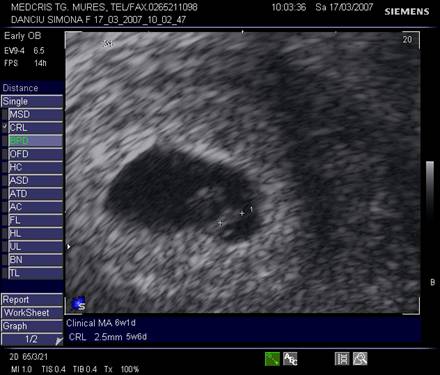

Fig. nr.104 Sarcina normala de 5 saptamani la ecografia transvaginala

Fig. nr.107 Dezvoltarea embrionului si a anexelor , la o sarcina de 7 saptamani.

( adaptat dupa Merz[13])